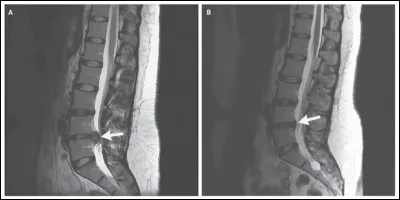

L'IRM est particulièrement utile dans l'étude du système nerveux central (cerveau et moelle épinière) en offrant une meilleure résolution que le scanner. Ci-contre, on peut observer une hernie discale qui, si elle est située au niveau des vertèbres L5-S1, peut se traduire cliniquement par...